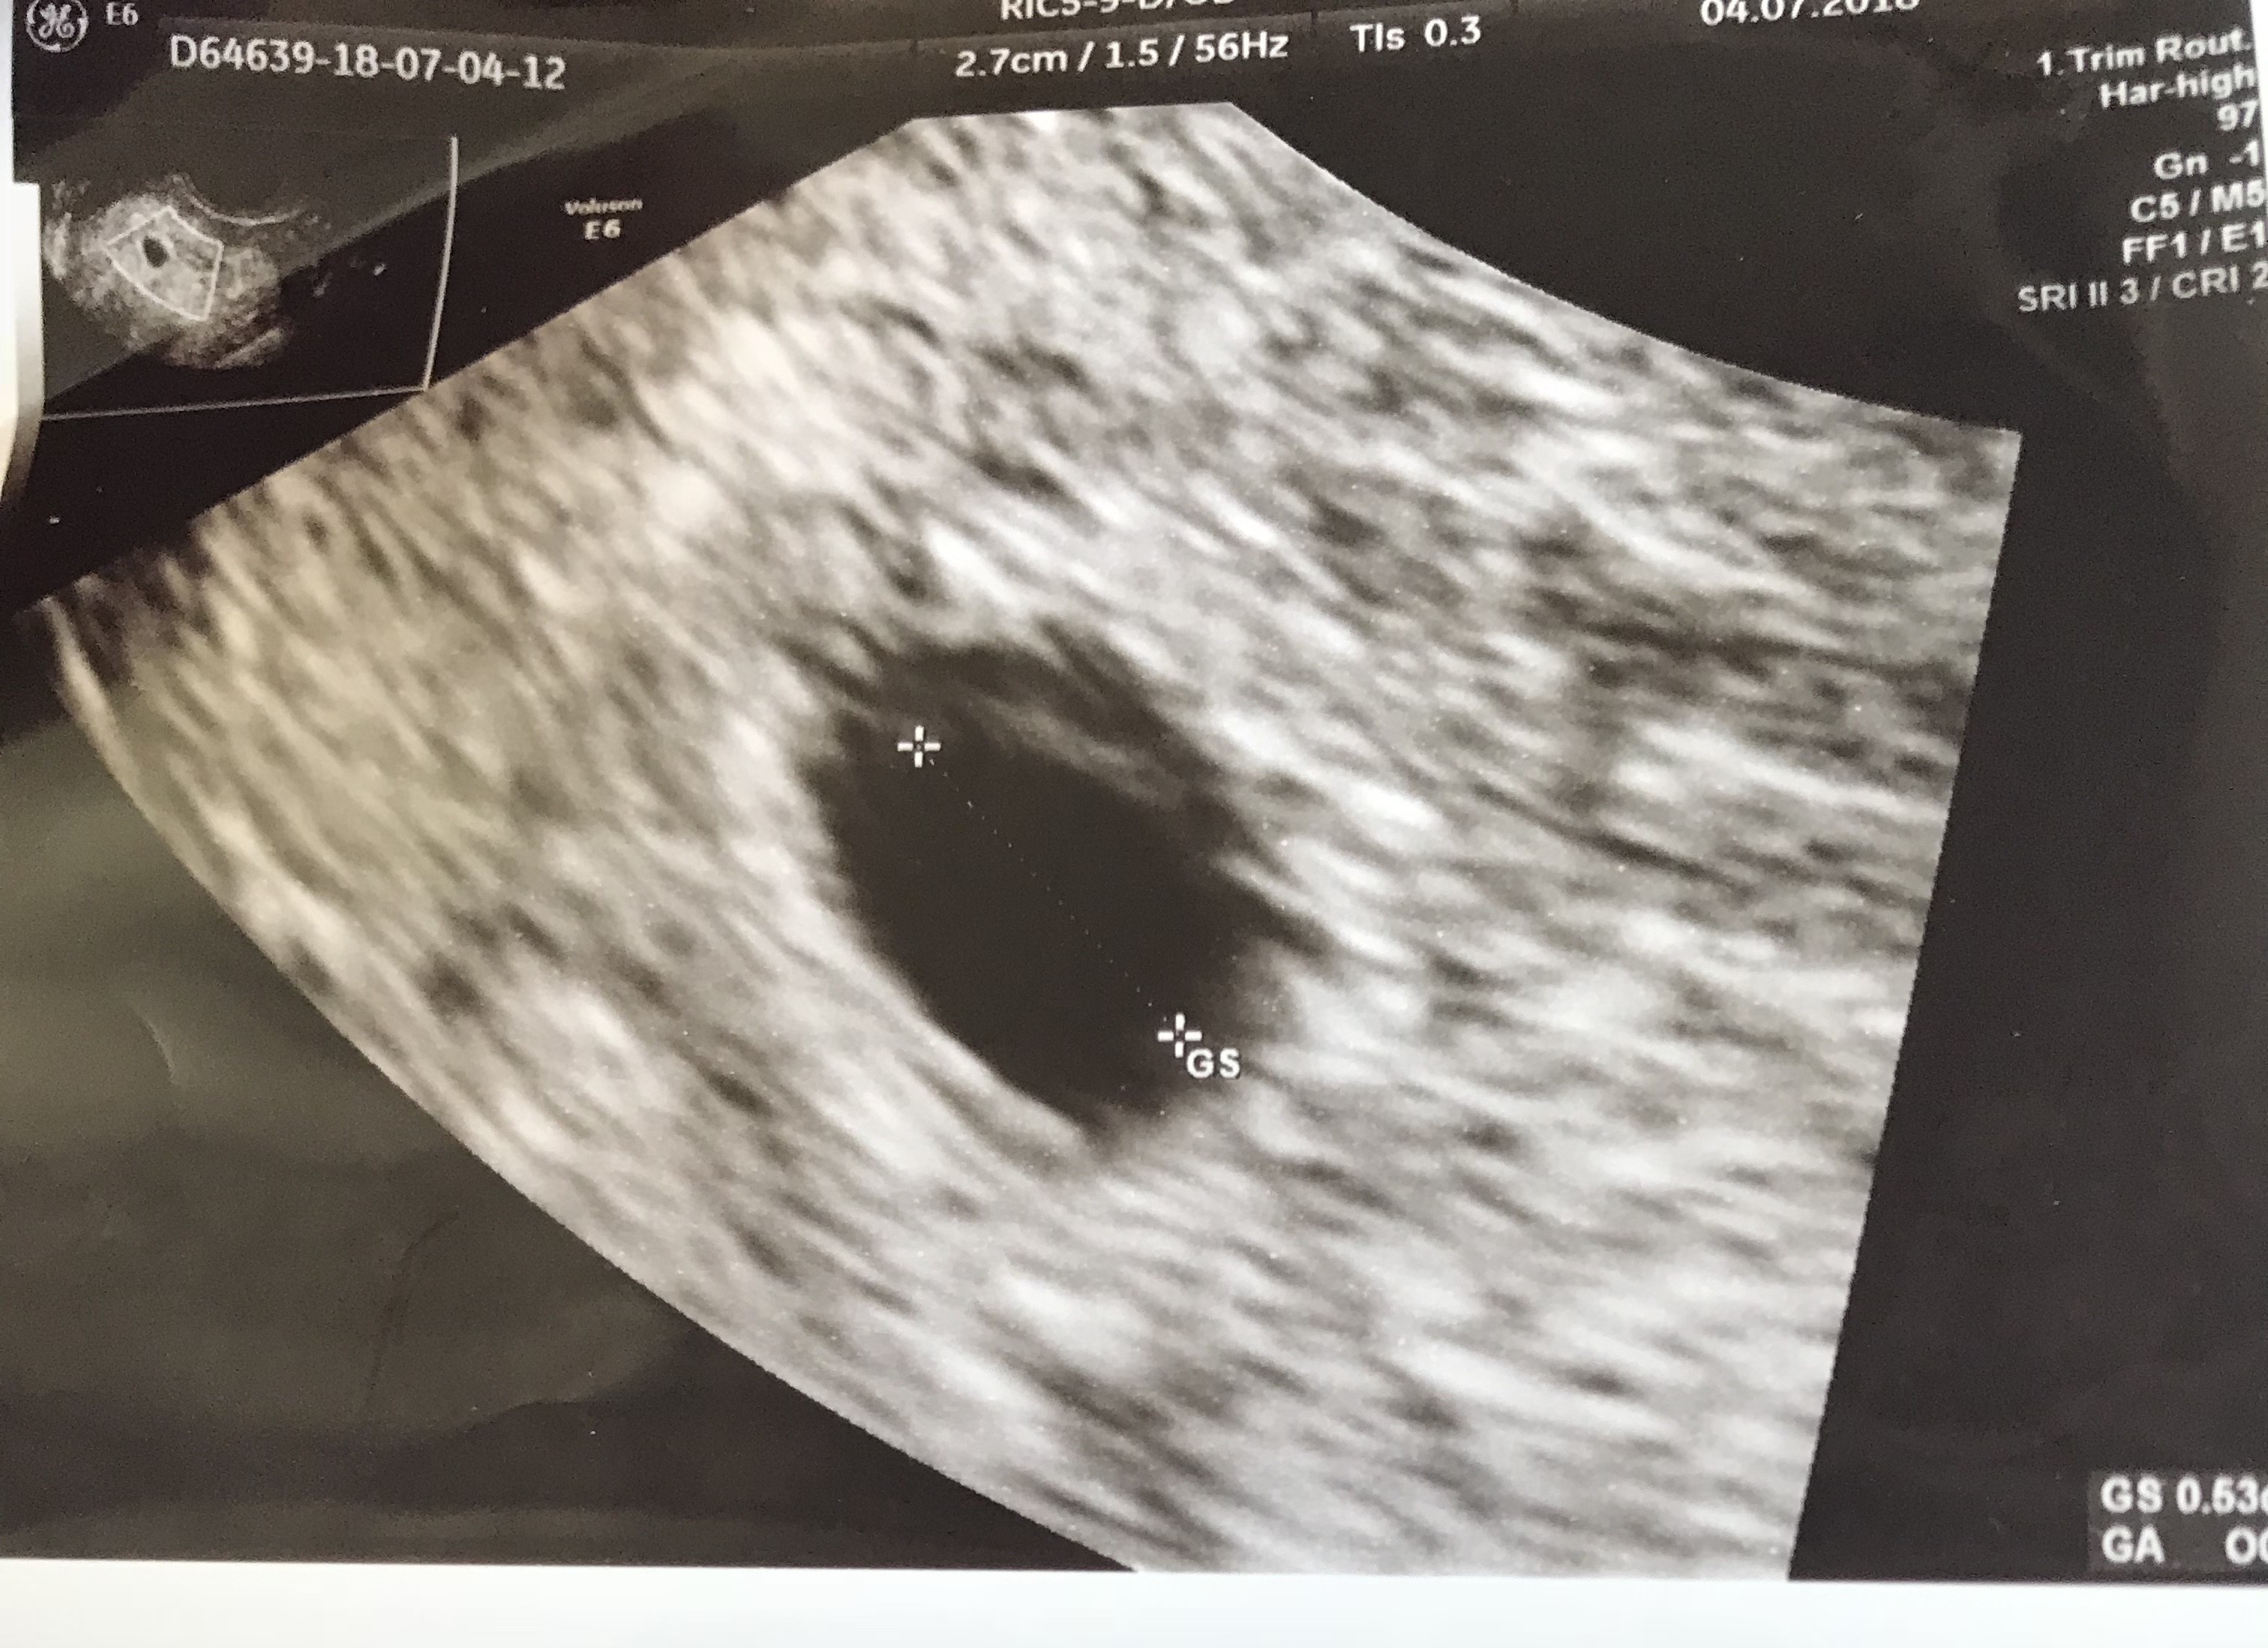

U mnie wyglada tak... ale ja w tym pęcherzyku coś widze, może sie myle, ale lekarz tez stwierdził ze może w tym miejscu sie coś pojawić - widzicie taka kreseczkę u góry? Tylko właśnie ta beta... gdybym jej nie robiła czekałabym po prostu do wizyty 12.07 ;(